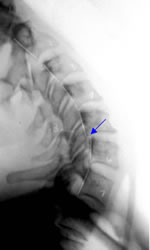

This extension x-ray image

illustrates ligamentous

instability at C5-C6.

The AMA Guides2 attribute

a 25% whole-person

impairment rating to those

who meet loss of motion

segment integrity criteria

in the cervical spine.